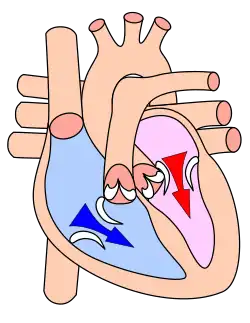

Le septum évite le passage direct du sang. Les valves assurent le passage unidirectionnel coordonné du sang depuis les atria vers les ventricules. Le cœur droit est dit veineux (ou segment capacitif), et le cœur gauche est dit artériel (ou segment résistif). Les parois des ventricules sont plus épaisses, et leur contraction est plus importante pour la distribution du sang contre la résistance artérielle.

Du sang appauvri en oxygène par son passage dans le corps entre dans l'atrium droit par trois veines, la veine cave supérieure (vena cava superior), la veine cave inférieure (vena cava inferior) et le sinus coronaire. Le sang passe ensuite vers le ventricule droit. Celui-ci le pompe vers les poumons par l'artère pulmonaire.

Après avoir perdu son dioxyde de carbone dans les poumons et s'y être pourvu de dioxygène, le sang passe par les veines pulmonaires vers l'oreillette gauche. De là le sang oxygéné entre dans le ventricule gauche. Celui-ci est la chambre pompante principale, ayant pour but d'envoyer le sang par l'aorte vers toutes les parties du corps.

Le ventricule gauche est bien plus massif que le droit parce qu'il doit exercer une force considérable pour forcer le sang à traverser tout le corps contre la pression corporelle, tandis que le ventricule droit ne dessert que les poumons.

Diastole et

Systole auriculaire

Systole ventriculaire

La fréquence cardiaque au repos chez l'Homme est de 60 à 80 battements par minute, pour un débit de 4,5 à 5 litres de sang par minute. Au total, le cœur peut battre plus de 2 milliards de fois en une vie. Chacun de ses battements entraîne une séquence d'événements collectivement appelés la révolution cardiaque. Celle-ci consiste en trois étapes majeures : la systole auriculaire, la systole ventriculaire et la diastole :

- Au cours de la systole auriculaire, les oreillettes se contractent et éjectent du sang vers les ventricules (remplissage actif). Une fois le sang expulsé des oreillettes, les valves auriculo-ventriculaires entre les oreillettes et les ventricules se ferment. Le sang continue tout de même à affluer dans les oreillettes. Ceci évite un reflux du sang vers les oreillettes. La fermeture de ces valves produit le son familier du battement du cœur.

- La systole ventriculaire implique la contraction des ventricules, expulsant le sang vers le système circulatoire. En fait, dans un premier temps, très bref, les valvules sigmoïdes sont fermées. Dès que la pression à l’intérieur des ventricules dépasse la pression artérielle, les valvules sigmoïdes s'ouvrent. Une fois le sang expulsé, les deux valves sigmoïdes - la valve pulmonaire à droite et la valve aortique à gauche - se ferment. Ainsi le sang ne reflue pas vers les ventricules. La fermeture des valvules sigmoïdes produit un deuxième bruit cardiaque plus aigu que le premier. La pression sanguine augmente.

- Enfin, la diastole est la relaxation de toutes les parties du cœur, permettant le remplissage (passif) des ventricules (plus de 80 % du remplissage dans les conditions usuelles), par les oreillettes droite et gauche et depuis les veines cave et pulmonaire. Les oreillettes se remplissent doucement et le sang s'écoule dans les ventricules.